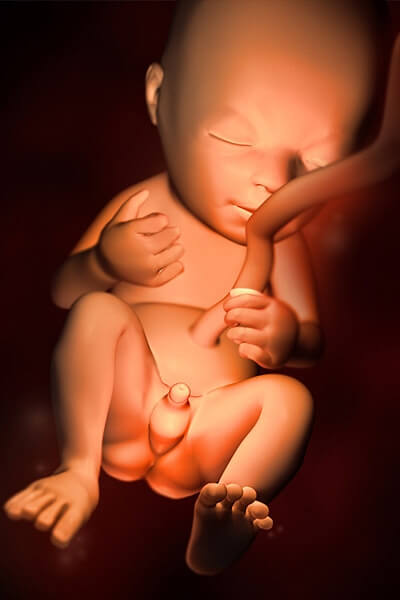

Малыш на 20 неделе беременности

За 20 недель кроха набрал 250-300 г и дорос до 17-18 см. Эти цифры приблизительные, поскольку каждый плод развивается индивидуально. На темпы роста и набор массы малышом в большой мере влияет образ жизни, питание и состояние здоровья мамы, а также генетические факторы (у низкорослых родителей, как правило, рождаются маленькие дети и наоборот).

На 20 неделе плод уже практически полностью сформированный, но вне матки он еще не жизнеспособен. Если проанализировать все, что происходило с крохой за последние недели, можно выделить несколько наиболее важных моментов:

- Тело покрылась пушковыми волосами и защитной смазкой, волосики появились и на голове, под тонкой кожицей начал откладываться жир.

- Полностью сформировались суставы рук и ног, теперь малыш может не просто дотрагиваться до чего-то, но и делать хватательные движения.

Что происходит с ребёнком на 20-й неделе беременности С этого срока рост ребёнка начинают указывать от макушки до пяток, а не до крестца, как это было раньше. Сейчас длина тела малыша в среднем равна 25 см, а вес — 300 г. Кожу плода покрывает толстый слой смазки. Она нужна для защиты от околоплодных вод.

Мимика плода на 20й неделе беременности становится всё более разнообразной: малыш улыбается, хмурится, морщит лоб, зажмуривается, опускает вниз уголки рта. Вес плода составляет 250-280 граммов, рост достиг 25-27 сантиметров. Теменно-копчиковая длина составляет около 16 сантиметров.